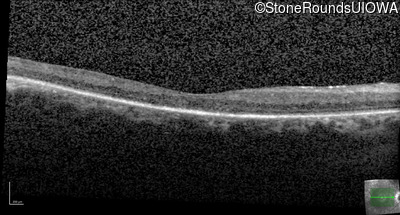

Optical Coherence Tomography - Left - 20/30 +2

Exemplar / OCT Stack

OCT Stack